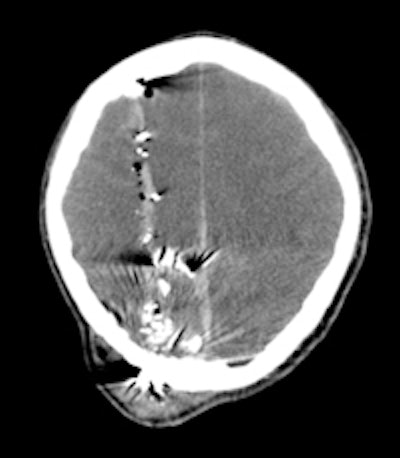

A 30-year-old male with a gunshot wound to the head. Left: Brain window axial CT image demonstrates a significant soft-tissue swelling and underlying fracture at the entry site of the projectile. The course of the bullet is seen by a linear hemorrhage through the right cerebral hemisphere. There is loss of the grey-white differentiation in keeping with a diffuse hypoxic injury. Right: The fragmentation and scatter of the low-velocity projectile is best seen on CT bone windows. All images courtesy of Dr. Andrew Shawyer.Doctors involved in the care of these patients need to understand the patterns and mechanisms of the injuries, he explained. To accurately interpret images of gunshot wounds, a basic knowledge of ballistics is important, especially the factors affecting the extent and type of tissue damage. Such knowledge is useful not only for evaluating acute injuries but also for determining the path of the missile, awareness of missile fragmentation, and embolization, thus contributing to the overall clinical, and often the forensic, picture.